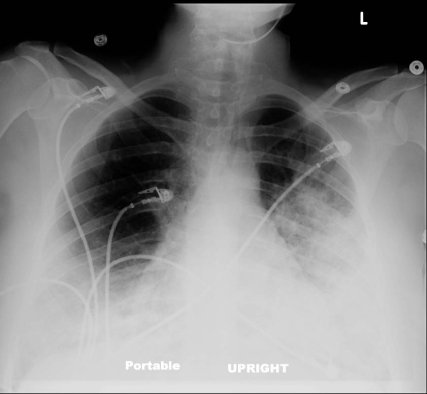

Chest Radiograph